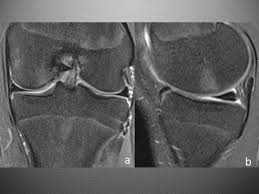

Lateral aspect of medial femoral condyle most common location. The motions of the condyles include rocking, gliding and rotating. In the knee, chondromalacia is usually related to injury, overuse of the knee, and poorly aligned muscles and bones around the knee joint. Methods sixteen knees with a small medial femoral. When ocd affects the knee, the most common location is within the lateral aspect of the medial femoral condyle. Medial condyle of femur from wikipedia, the free encyclopedia the medial condyle is one of the two projections on the lower extremity of femur, the other being the lateral condyle. The femoral condyle allograft has been used for resurfacing cartilage defects with mature hyaline cartilage for several decades, with very high success rates. The medial femoral condyle is supplied by a plexus of vessels from the descending genicular artery and the medial superior genicular artery.

They are called the medial and the lateral femoral condyle, respectively. An imbalance of the muscles around the knee (some muscles are weaker than others.) overuse (repeated bending or twisting) of the knee joint, especially during sports. However, two of the patients had one or more fractures missed when they first presented. The medial femoral condyles are the bony protrusions on the inside edge of the bottom of the femur bone in each thigh. Osteochondritis dissecans (ocd) is an acquired, reversible, idiopathic lesion. Osteonecrosis of the medial femoral condyle presents as a sudden onset of pain on the medial side of the knee. This is associated with a positive bone scan and, frequently, a radiolucent lesion in the subchondral zone. Methods sixteen knees with a small medial femoral. The medial condyle is larger than the lateral (outer) condyle due to more weight bearing caused by the centre of mass being medial to the knee. Medial condyle of femur from wikipedia, the free encyclopedia the medial condyle is one of the two projections on the lower extremity of femur, the other being the lateral condyle. Root tear (radial tear) of the medial meniscus mild or moderate knee arthritis Osteonecrosis of the medial femoral condyle can be treated in a variety of ways depending on the stage of the disease. Of the six patients who had suffered an isolated fracture of their medial condyle, four of the patients had their fractures diagnosed on the first visit.

The radiographs demonstrated abnormal contour of the medial femoral condyle, consistent with an osteochondral defect, and a fabella posterior to the knee. Methods sixteen knees with a small medial femoral. It acts to support a significant amount of the patient's body weight. An imbalance of the muscles around the knee (some muscles are weaker than others.) overuse (repeated bending or twisting) of the knee joint, especially during sports. If there is a fracture (break) in part of the condyle, this is known as a fracture of the femoral condyle. The medial femoral condyle is supplied by a plexus of vessels from the descending genicular artery and the medial superior genicular artery. Damage may also be the result of a direct blow to the knee. Palpable to either side of the knee joint when it is bent, they are known specifically as the medial and lateral femoral condyles.

An articular cartilage injury, or chondral injury, may occur as a result of a pivot or twist on a bent knee, similar to the motion that can cause a meniscus tear. An imbalance of the muscles around the knee (some muscles are weaker than others.) overuse (repeated bending or twisting) of the knee joint, especially during sports. Juvenile ocd lesions have a better healing prognosis than adults. Osteonecrosis of the medial femoral condyle presents as a sudden onset of pain on the medial side of the knee. The radiographs demonstrated abnormal contour of the medial femoral condyle, consistent with an osteochondral defect, and a fabella posterior to the knee. Please see our knee injury protocol for additional information on this topic. Chondral injuries may accompany an injury to a ligament, such as the anterior cruciate ligament. Medial condyle of femur from wikipedia, the free encyclopedia the medial condyle is one of the two projections on the lower extremity of femur, the other being the lateral condyle. In the knee, chondromalacia is usually related to injury, overuse of the knee, and poorly aligned muscles and bones around the knee joint. The motions of the condyles include rocking, gliding and rotating. One presumed mechanism of injury is a stieda fracture (avulsion injury of the medial collateral ligament at the medial femoral condyle). Generally, ocd seems to affect males more commonly than females (between 2:1 and 3:1). According to the hospital for special surgery, the medial femoral condyle is the inside of the knee, and health issues dealing with it can be treated.